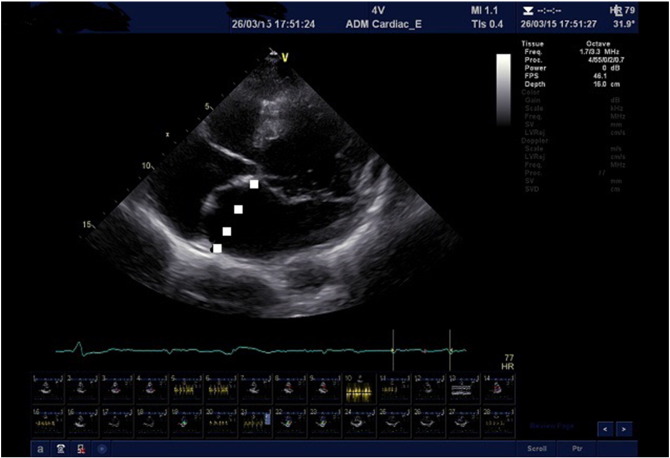

An asymptomatic 58-year old Caucasian woman requested a second opinion prior to mitral valve replacement due to severe mitral valve prolapse and apparent severe left atrial enlargement. Atrial fibrillation and stigmata of Marfan syndrome was noted, but no other clinical abnormalities were present. Fig. 1 is a two-dimensional, transthoracic echocardiographic image of the left atrium which demonstrates mitral valve prolapse of both the anterior and posterior mitral valve leaflets, as well as a prominent interatrial septal aneurysm which bulges into the right atrium. No echocardiographic stigmata of left ventricular dysfunction were present.

Transthoracic, two-dimensional echocardiographic image demonstrating prolapse of ...

Fig. 1.

Transthoracic, two-dimensional echocardiographic image demonstrating prolapse of both the anterior and posterior mitral valve leaflets with an interatrial septal aneurysm which bulges into the right atrium.